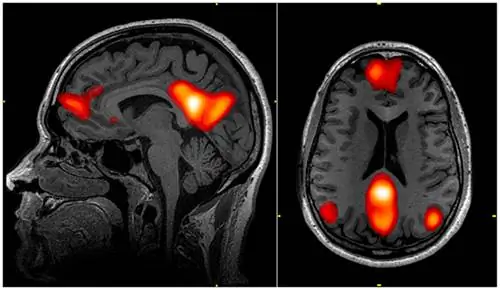

Изображение мозга с выделением областей, связанных с сетью режима по умолчанию.

Во-первых, исследователи провели серию когнитивных тестов, таких как Калифорнийский тест на словесное обучение (CVLT) и Тест на создание следов (TMT). Семнадцать участников старшей группы набрали не меньше среднего балла младшей группы. То есть этих 17 человек можно было считать суперстариками, выступающими на том же уровне, что и более молодые участники исследования. Помимо этих людей, члены старшей группы, как правило, хуже справлялись с когнитивными тестами. Затем исследователи просканировали мозг всех участников с помощью фМРТ, уделяя особое внимание двум частям мозга: сети режима по умолчанию и сети заметности.

Сеть режима по умолчанию - это, как можно предположить из ее названия, ряд областей мозга, которые активны по умолчанию - когда мы не заняты какой-либо задачей, они, как правило, проявляют более высокий уровень активности. Это также, по-видимому, очень связано с мыслями о себе, мыслями о других, а также с аспектами памяти и мыслями о будущем.

Сеть значимости - это еще одна сеть областей мозга, названная так потому, что она тесно связана с обнаружением и интеграцией значимых эмоциональных и сенсорных стимулов. (В неврологии значимость означает, насколько элемент «выделяется»). Обе эти сети также чрезвычайно важны для общей когнитивной функции, и у пожилых людей активность в этих сетях была более скоординированной, чем у их сверстников.